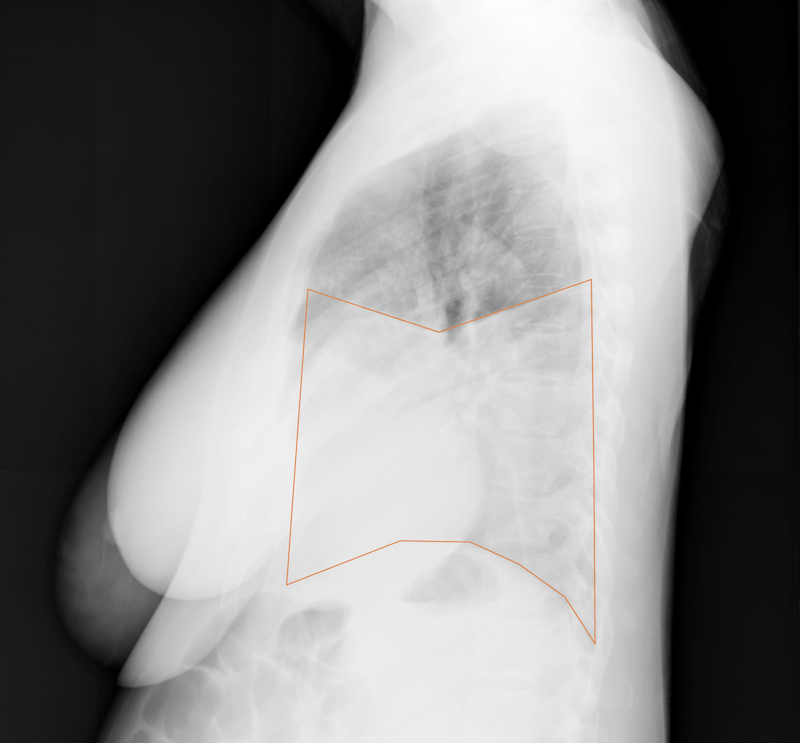

Diagnostic testing. A computed tomography (CT) scan of the chest demonstrated a large right-sided pleural effusion and bilateral airspace opacities (Figures 1 and 2). A thoracentesis was performed. The pleural fluid was milky in consistency and laboratory testing of the fluid showed a high triglyceride content of 474 mg/dL. Radiological findings showed multifocal ground glass opacities and septal thickening (pattern of “crazy paving”) with additional confluent consolidations (Figure 3). Subsequent bronchoalveolar lavage revealed hemosiderin-laden macrophages and atypical lymphocytes, but cultures remained negative, although a respiratory polymerase chain reaction was reactive for Haemophilus influenzae. She also had an elevated b-type naturetic peptide level of 484 pg/mL.

Figure 1b. The lateral view of the chest X-ray demonstrating a large right-sided pleural effusion (orange overlay).